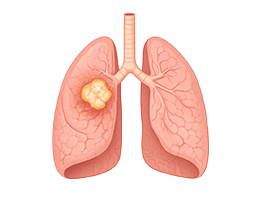

폐렴 (Pneumonia)

기관지염 (Bronchitis)

폐결핵 (Pulmonary Tuberculosis)

만성폐쇄성폐질환 (Chronic Obstructive Pulmonary Disease)

폐기종 (Emphysema)

폐농양 (Lung Abscess)

폐혈증 (Pulmonary Sepsis)

폐색전증 (Pulmonary Embolism)

폐섬유증 (Pulmonary Fibrosis)

간질성폐질환 (Interstitial Lung Disease)

특발성폐섬유증 (Idiopathic pulmonary fibrosis)

비결핵항산균폐질환 (Nontuberculous mycobacterial lung disease)

흡인폐렴 (Aspiration pneumonia)